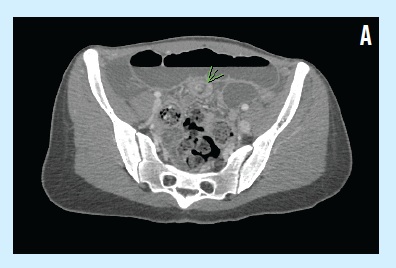

However, 1 month later, she was hospitalized again after presenting with epigastric pain and bilious vomiting for 2 days. A pediatric surgeon was consulted out of concern for possible small bowel obstruction. The patient received nothing by mouth, and an abdominal computed tomography (CT) scan done on the day of admission showed evidence of ileoileal intussusception in the left lower quadrant and resultant small bowel obstruction (A).

She then was hospitalized due to suspicion of a small bowel obstruction, which could have been a direct effect of the bezoar. Intestinal obstruction also can be secondary to intussusception, which was an abdominal CT finding on the day of admission in this patient’s case. No intussusception was identified intraoperatively, however; we hypothesize that it could have resolved after the enemas.